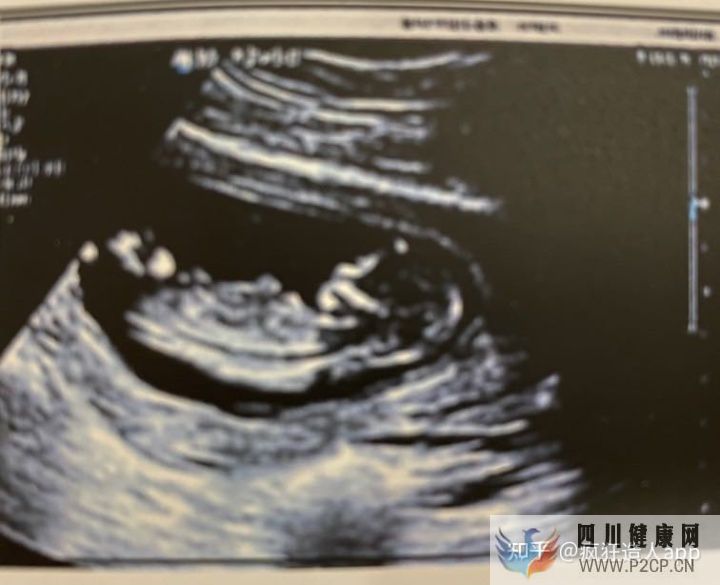

后来试管毕业去建档医院做NT看到宝宝这个B超图的时候,激动的眼泪都流出来了。

这一路的艰辛真的只有经历的姐妹才能明白和懂得,我这还是检查没有问题,只是我老公严重少弱精,但是他只需要取精就好了,真正难的是女人,记不清楚肚子上扎了多少针,胳膊上抽了多少管的血,有时候扎的胳膊青的那一块儿隔了一礼拜还没有下去,但幸运的是结果是好的,我已经很知足了,也感谢老天爷赐给我了一个健康漂亮的小宝宝,也希望这份幸运每个姐妹都能拥有。